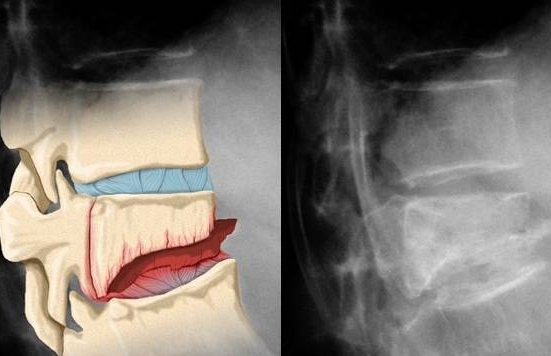

Грудной отдел позвоночника отличается ограниченной подвижностью, что позволяет поврежденному позвонку оставаться на месте длительное время. Однако обычно наблюдается уменьшение его высоты и возможное образование трещины. Чаще всего травмируются 12, 11 или 7 грудные позвонки, что связано с анатомическими особенностями человеческого скелета. К сожалению, поврежденные элементы постепенно разрушаются при любых движениях, включая кашель или чихание. Боль в этом случае часто ошибочно воспринимается как проявление остеохондроза.

Обследование пациента начинается с тщательного сбора анамнеза. Врач выясняет, когда произошел компрессионный перелом, а также определяет наличие сопутствующих заболеваний и дополнительные жалобы. Основные методы диагностики включают:

- рентгенографию для оценки общего состояния;